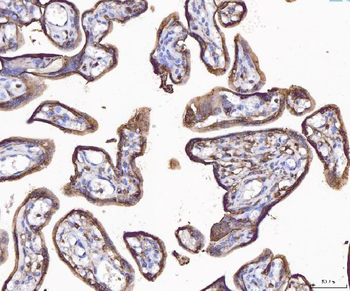

10 μg, 100 μg - Anti-HSD11B2 Antibody [orb316541]

IF, IHC, IHC-Fr, WB

Human, Mouse, Rat

Rabbit

Polyclonal

Unconjugated

10 μg, 100 μg - Anti-CD44 Antibody [orb402179]